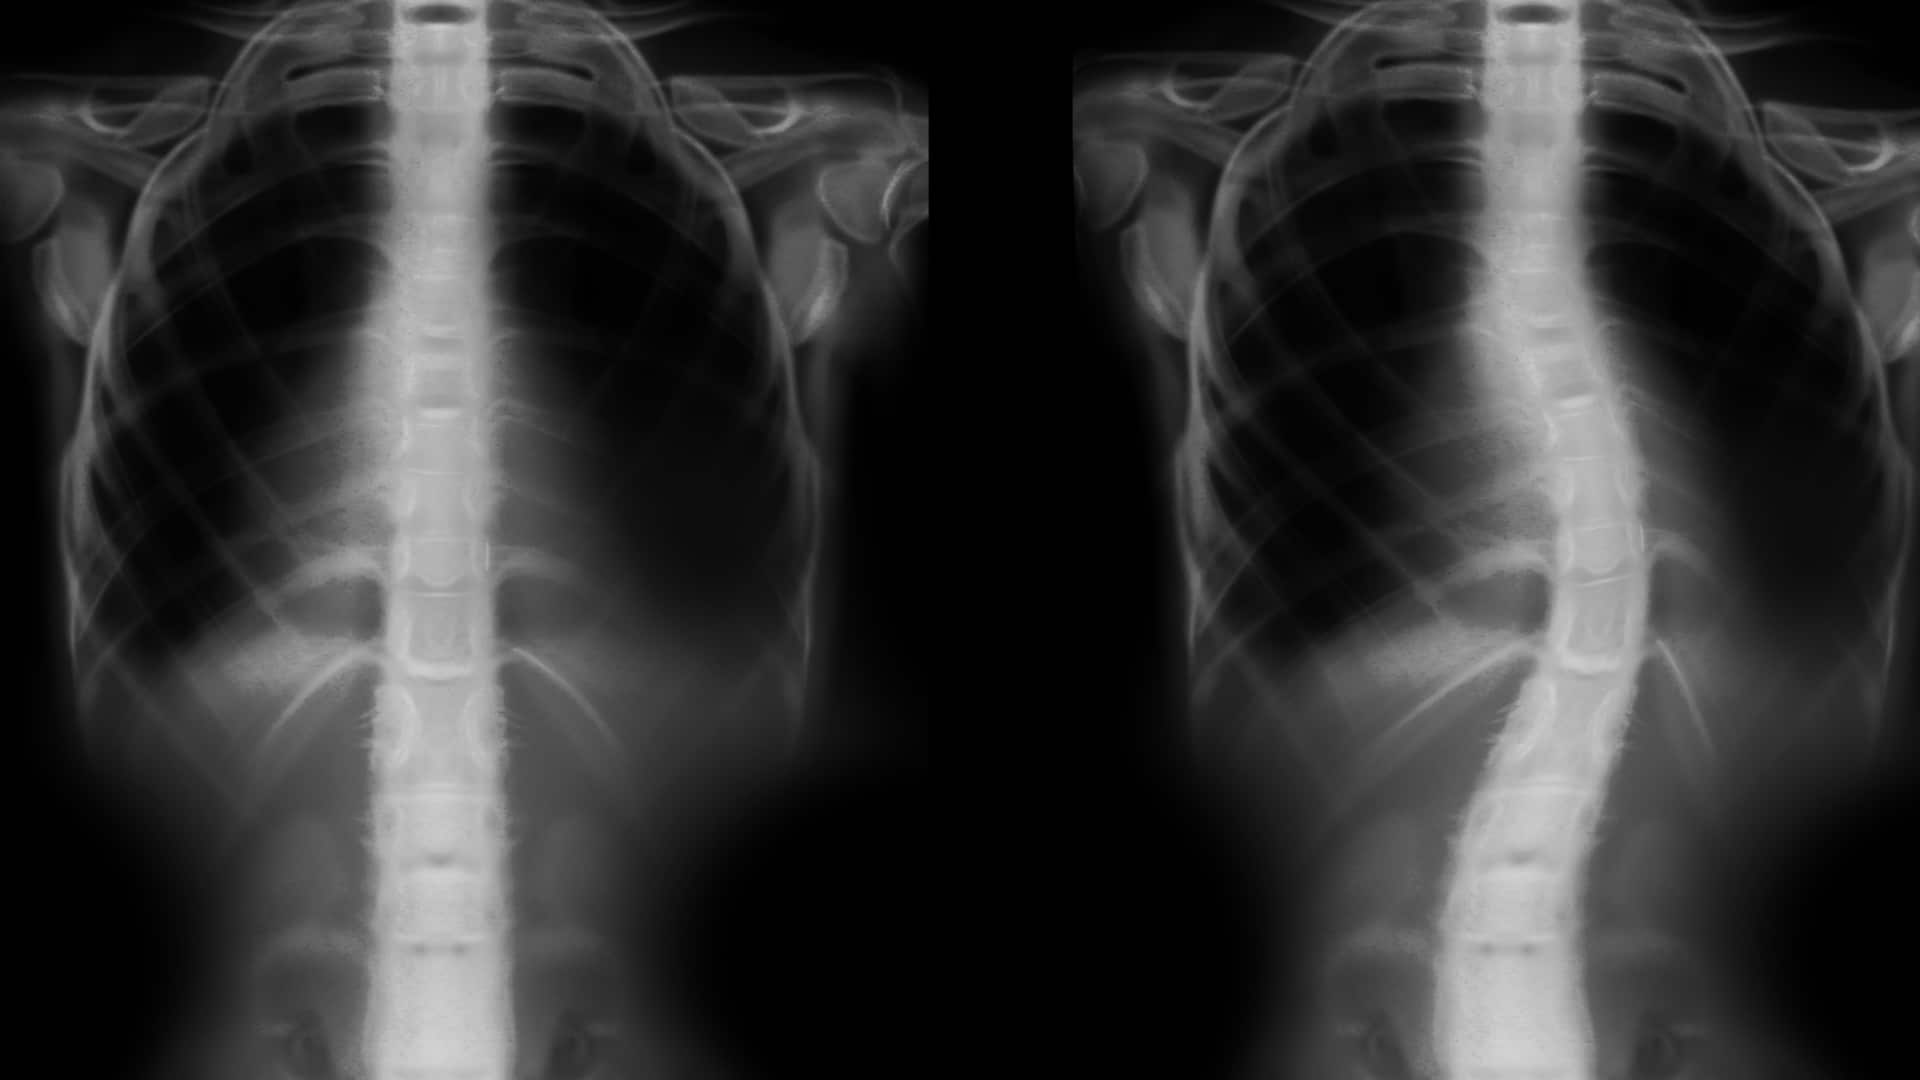

- угол искривления (по рентгену измеряют угол Кобба).